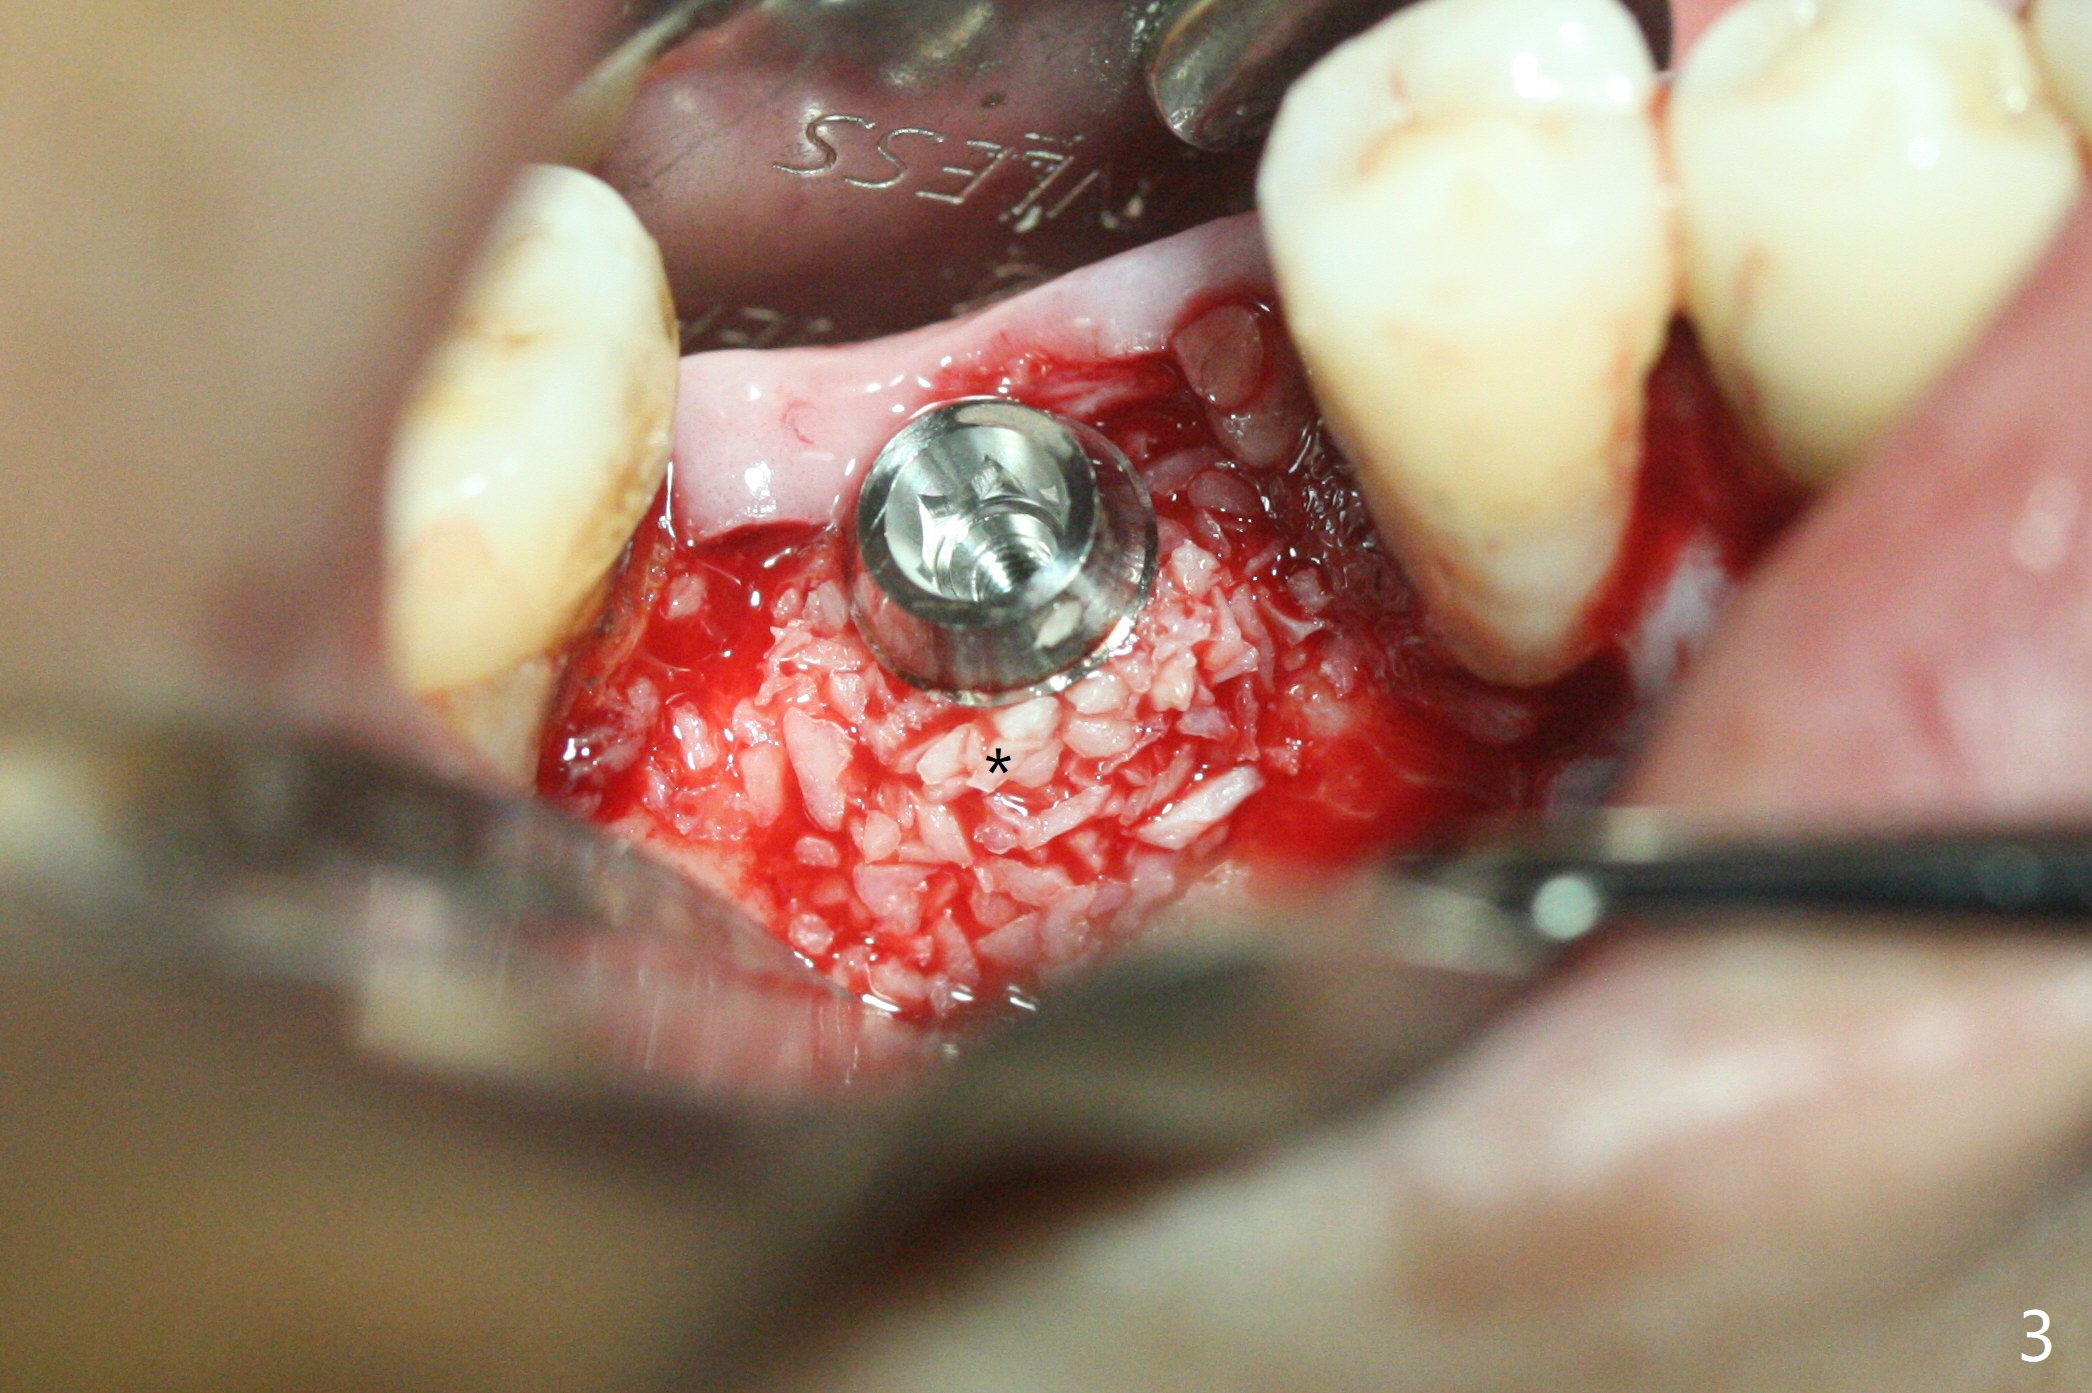

A 5x12 mm SM implant with periimplantitis at #30 is removed with a 5/6 mm trephine bur, small elevator and implant driver. A 3.8 mm Magic drill is used to start a new osteotomy in the lingual wall of the old one free hand. With the final drill (4.8x13 mm), a 5x11(3) mm Magicore is placed (Fig.1-4). The large buccal gap (Fig.2 arrowheads) is filled with allograft (Fig.3 *). The latter is covered by PRF, followed by suture. Periodontal dressing is applied around the 4.2x3 mm solid abutment and the coronal portion of the Magicore (Fig.4 <). The green outline in Fig.5 (CT coronal section) represents a new 5x10 mm implant (design), while the thick red line is approximately the long axis of the new implant. The implant heals in spite of buccal recession. Impression is taken with placement of a 4.3x5 mm solid abutment 4.5 months postop (Fig.6). Take follow-up CT to determine buccal bone formation.